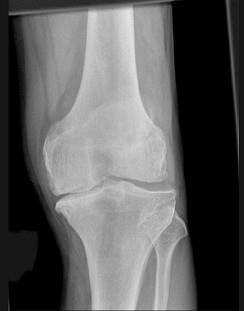

问题 男,76岁,左膝关节长久站立时疼痛,可扪及捏发音,请结合图像,选出最可能的诊断 ( )

选项 A、创伤性关节炎 B、肥大性骨关节病 C、畸形性骨炎 D、神经性关节病 E、退行性骨关节病

答案 E